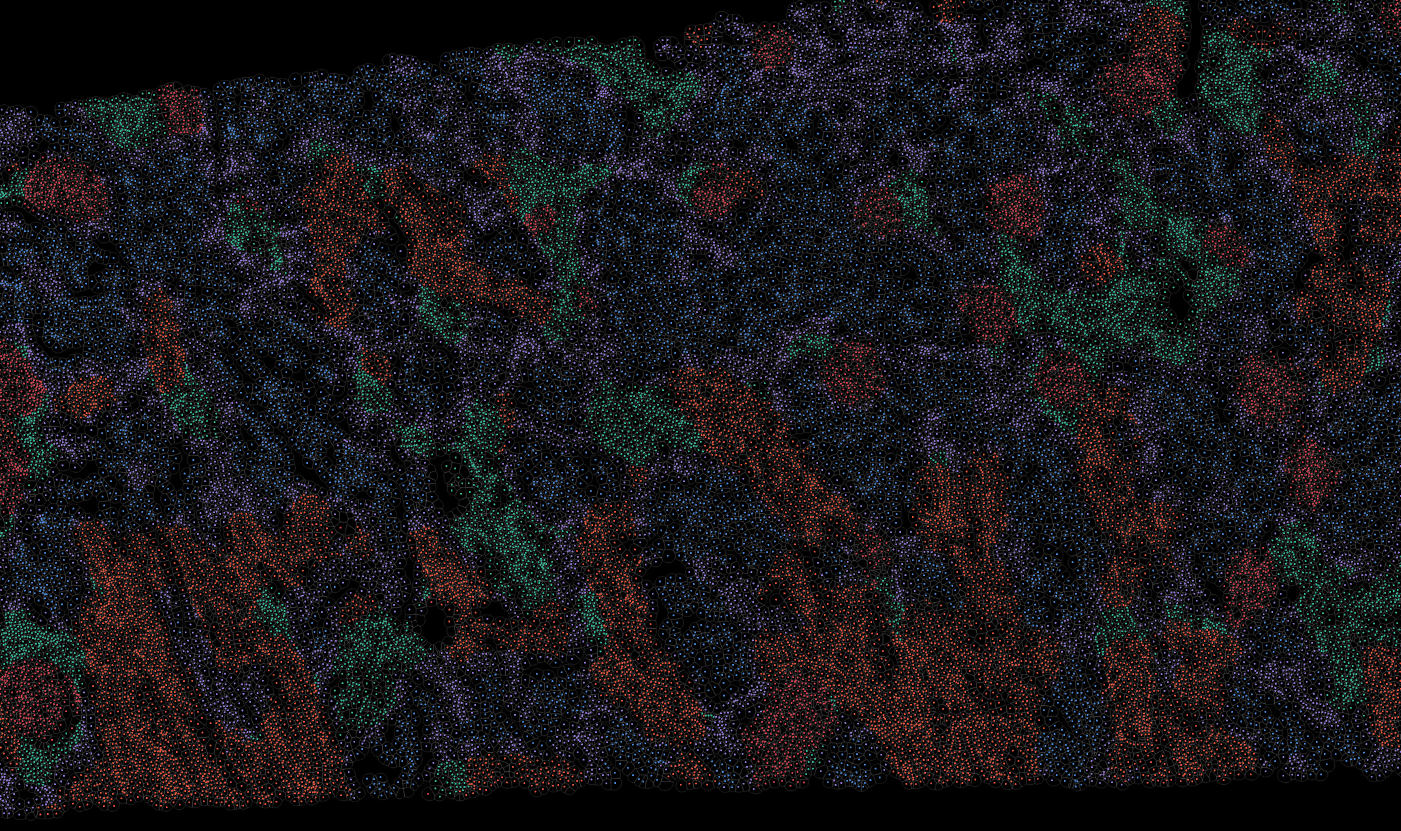

Just as cell type labels are fundamental to single-cell data analysis, tissue annotation is equally crucial for understanding spatial organization and biological context. In spatial transcriptomics, identifying tissue structures helps researchers interpret gene expression patterns, uncover spatially restricted cell states, and study disease-associated microenvironments with far greater clarity.

To support this essential analytical step, OmnibusX now integrates a dedicated tissue segmentation module directly into the desktop application. This feature brings structure-level understanding to your spatial datasets, without requiring additional tools, cloud resources, or complex model development.

The segmentation module is designed to generalize across a wide range of biological tissues. Below are representative benchmark results based on 10x Genomics demo datasets:

Applicability across different spatial resolutions

The segmentation module is designed to help researchers explore tissue architecture at multiple levels of detail, depending on their scientific question. Users can begin by dividing the tissue into major anatomical structures to gain a broad overview of the spatial landscape. From there, they can zoom into a specific region of interest and further segment it into sub-tissue compartments, enabling more refined analysis of microenvironments and localized biological processes.